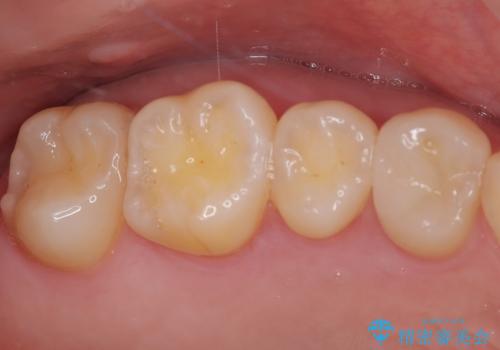

詰め物が欠けた セラミックインレーによる修復

- 以前治療した詰め物が欠けてしまったことを主訴として来院した患者様です。

食べ物がはさまったり、冷たいものがしみるといった症状がみられました。

むし歯の染め出し液と拡大鏡を用いて、むし歯がないことを確認し、

セラミックインレーにて修復することとしました。

食べ物がはさまりにくくなり、冷たいものがしみる症状もなくなり、大変満足していただきました。